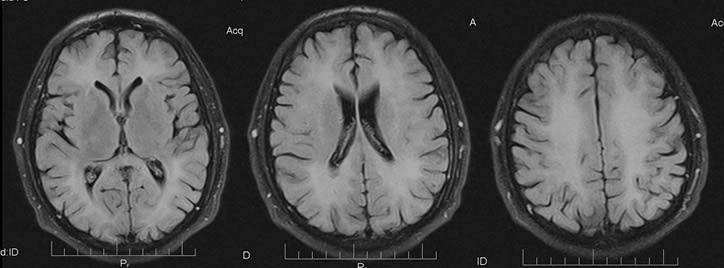

Первые 3 дня пребывания дома занимался домашними делами, водил автомобиль. Далее стал заторможённым, перестал отвечать на вопросы, «замкнулся в себе». Консультирован психиатром с последующей госпитализацией в психоневрологическое отделение, где находился в течение 2 дней. Консультирован неврологом, который отметил выраженные когнитивные расстройства, дезориентацию больного в собственной личности и времени, ограниченное выполнение команд; неубедительную анизорефлексию (d ≥s). Выписан с диагнозом: «G93.8. Токсическая энцефалопатия в форме грубых когнитивных расстройств». Проведена МРТ головного мозга (рис. 1), заключение: «Диффузная лейкоэнцефалопатия. Убедительных данных за объёмный процесс головного мозга, острое ишемическое поражение и интракраниальную геморрагию нет».

Рис. 1. Магнитно-резонансная томограмма головного мозга пациента Н. при поступлении в неврологическое отделение

«Светлый промежуток» с отсроченностью клинических проявлений обусловлен, с одной стороны, определёнными сроками, которые необходимы для формирования иммунного ответа (поздний иммунный ответ формируется через 96 ч и более), с другой стороны — постепенно нарастающим в результате иммунного повреждения поражением нервной ткани. Данное предположение подтверждается результатами нейровизуализации в динамике — у больного по данным МРТ, сделанной на 2-й день после первых симптомов ОПЛ, уже определялись очаги демиелинизации (см. рис. 1), площадь их вместе с нарастанием клинических симптомов увеличивалась (см. рис. 2, 3).